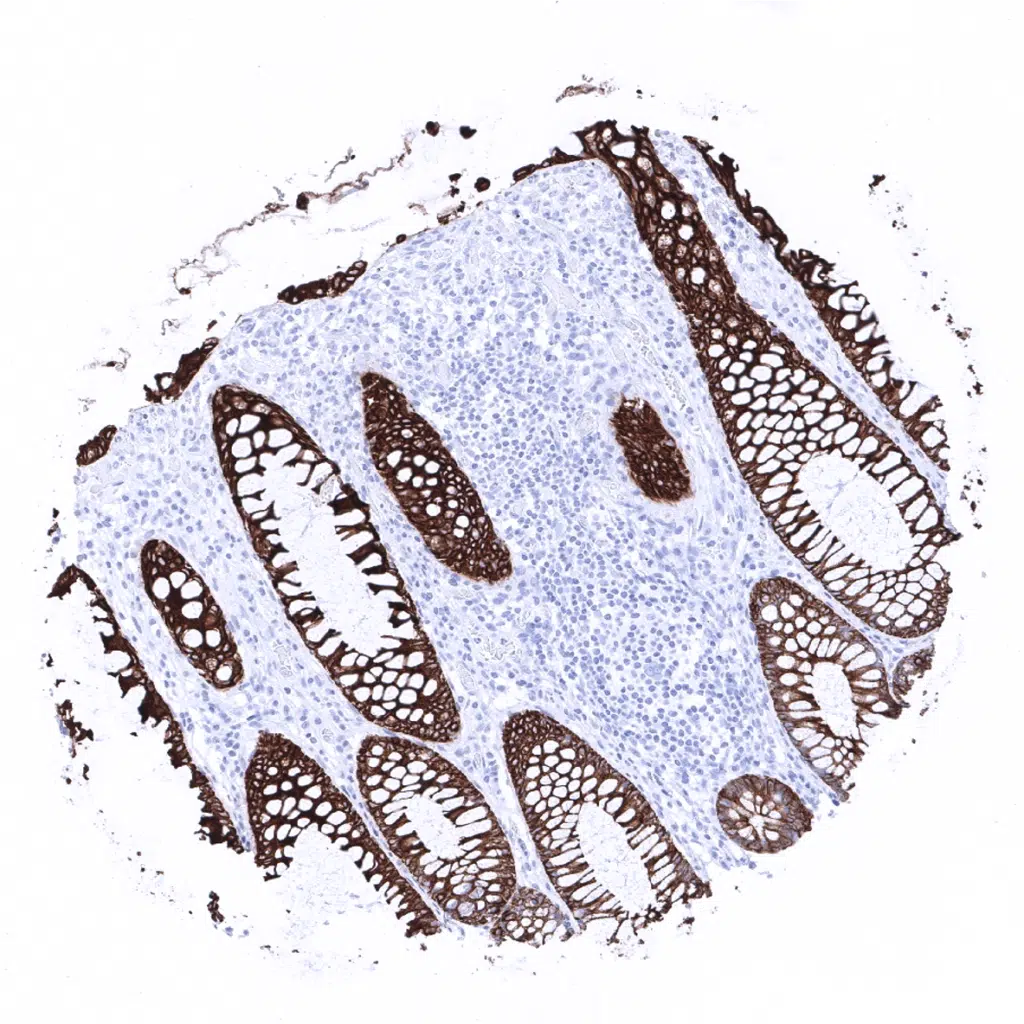

Colon descendens, mucosa - Strong Cytokeratin 19 staining of all epithelial cells.